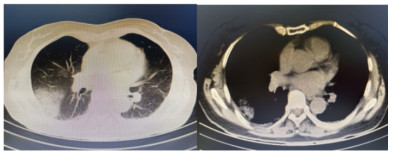

患者,女,64岁,居住农村,既往有糖耐量异常5年,未正规治疗,4年前诊断为“原发性甲状腺功能亢进”,经治疗已好转。无高风险、中风险地区旅居史,无境外旅居史,无新冠病毒肺炎确诊或疑似患者接触史。2020年7月31日患者无明显诱因下在家中出现发热,体温最高39.4 ℃,伴畏寒、全身乏力,无胸闷、胸痛,无咳嗽、咳痰,无腹痛、腹泻,无黑矇、晕厥,遂在家中自服“退热药”后体温降至正常,但体温仍有反复。8月2日早晨患者再次出现发热,伴畏寒、寒战,遂至本院发热门诊就诊,予查C-反应蛋白156 mg/L,降钙素原0.64 ng/L,考虑感染性发热,遂予“哌拉西林他唑巴坦钠4.5 g每12 h一次”静滴抗感染治疗,后患者突发呼吸费力,伴咳嗽、咯血,为鲜红色血液,量较多,遂于8月2日14:18送达本院急诊抢救室。来时患者呼吸急促,有咳嗽伴咳血性痰,双侧小腿持续性钝痛,查体:血压188/86 mmHg(1 mmHg=0.133 kPa),心率168次/min,呼吸36次/min,血氧饱和度50%,体温38.6 ℃。神志清,精神软,急性面容,双侧结膜略充血,全身皮肤黏膜未见明显充血、淤血,未触及淋巴结肿大。口唇微绀,两肺呼吸音粗,可闻及明显湿性啰音,心律齐,无明显病理性杂音;腹平软,无压痛反跳痛,四肢肌力Ⅴ级,两侧病理征未引出。予心电监护、特级护理、面罩吸氧、建立静脉通道,送检血常规、生化、血气、心肌酶、凝血酶原时间系列、痰培养等常规检查,同时予送检血标本行高通量测序,完善胸部CT检查(图 1)。辅助检查结果如下:8月2日胸腹部CT示两肺感染,腹部未见明显异常。血常规:白细胞计数7.9×109/L,中性粒细胞百分比89%,血红蛋白121 g/L,血小板计数104×109/L,C-反应蛋白156.82 mg/L。血生化:丙氨酸氨基转移酶51 U/L,天门冬氨酸氨基转移酶63 U/L,白蛋白34.5 g/L,总胆红素17.4 mmol/L,肌酐74 mol/L。心肌酶谱:心肌肌钙蛋白I 0.014 ng/mL,肌红蛋白322 ng/mL,肌酸激酶同工酶3.2 ng/mL。血气分析:pH 7.435,二氧化碳分压29 mmHg,氧分压53.5 mmHg,K+ 2.6 mmol/L,Na+ 132 mmol/L,血乳酸3.1 mmol/L。新型冠状病毒抗体、核酸阴性。接诊医师初步诊断为“咯血待查:疑似肺部感染,呼吸衰竭”,治疗上予亚胺培南0.5 g静滴经验性抗感染、甲泼尼龙80 mg静滴抗炎,同时予化痰、平喘等对症、支持。17:00患者出现呼吸费力加重,10 L/min面罩吸氧下血氧饱和度仍为70%,故予紧急气管插管、机械通气,随后转入ICU,联系感染科医师会诊,结合患者病史及CT影像学表现的广泛、片状密度增高影特点,考虑钩端螺旋体病可能性大,不排除“赫氏反应”,故继续予亚胺培南0.5 g静滴每6 h一次抗感染、甲泼尼龙80 mg静滴每12 h一次抗炎、白蛋白营养支持等治疗。8月3日更改甲泼尼龙80 mg静滴每天一次。8月4日高通基因测序回报:检测出问号钩端螺旋体DNA,符合入院时推断,明确病原体后予修正诊断为肺出血型钩体病伴赫氏反应。8月5日停亚胺培南,改青霉素160万单位静滴每8 h一次。8月8日患者病情稳定,拔除气管导管,予甲泼尼龙减量为40 mg静滴1次/d,8月9日复查胸部CT提示两肺斑片状、片状密度增高影较前有所吸收(图 2),停用甲泼尼龙。8月10日转入呼吸科。8月17日复查胸部CT提示两肺斑片状、片状、条索状密度增高影,较前明显吸收(图 3)。8月20日患者好转出院。9月18日随访,复查CT提示两肺散在条索状密度增高影,基本恢复正常(图 4)。

图 4 9月18日患者随访时胸部CT示两肺散在条索状密度增高影,基本恢复正常